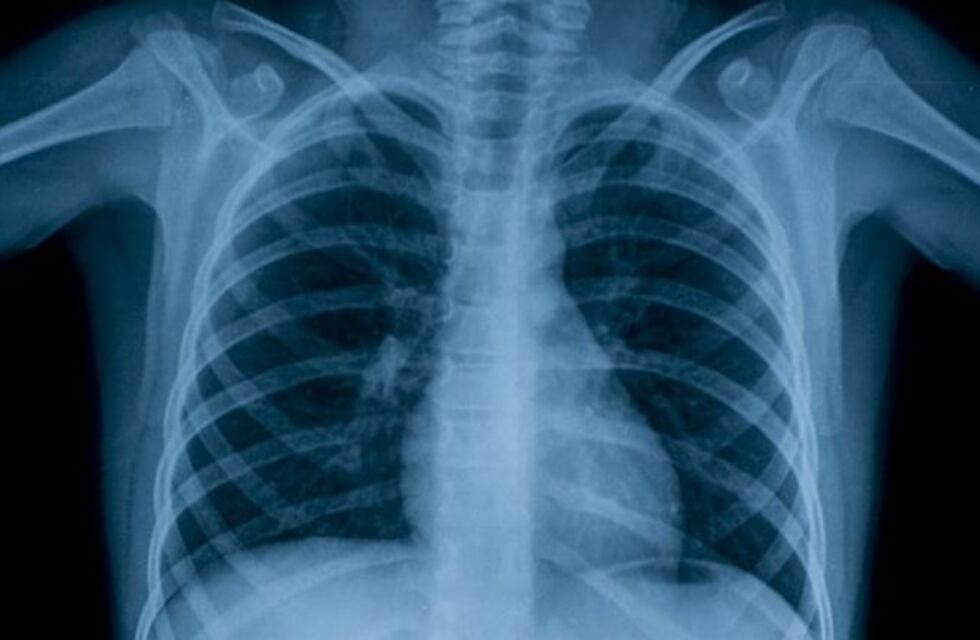

Luego de que se conociera un caso de tuberculosis en la escuela "Joaquín Castellanos" del barrio salteño de Tres Cerritos, el Ministerio de Salud de la provincia confirmó que cada año se detectan alrededor de 800 casos positivos en Salta.